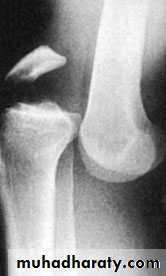

Tibial plateau fractures:Direct blow or fall from height may cause fracture of one tibial condyle or both. Fracture lateral condyle is the commonest named as bumper fracture caused by a force that abducts the tibia upon femur while the foot is fixed on ground. Patient usually is an adult, the knee joint is swollen, bruises, there is diffuse tenderness and doughy feel of haemarthrosis.ligaments injuries must be excluded.

Imaging : X-ray: anteroposterior, lateral & oblique

views. ct -Scan may used to detect amount of depression and comminuation.

Tibial plateau fracture